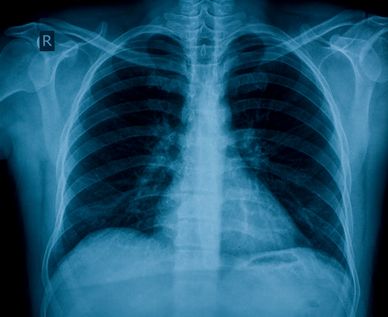

The lungs are a specialized type of chamber whose function operates automatically according to the principles of physics and mechanics. Due to their material composition, structural design, geometric configuration, and anatomical position within the body, they enable one of the most vital physiological exchanges essential for sustaining life.

Within this system, the lungs serve solely as passive chambers.

Throughout this process, the lungs remain passive, filled and emptied by the movement of surrounding structures, not by their own muscles.